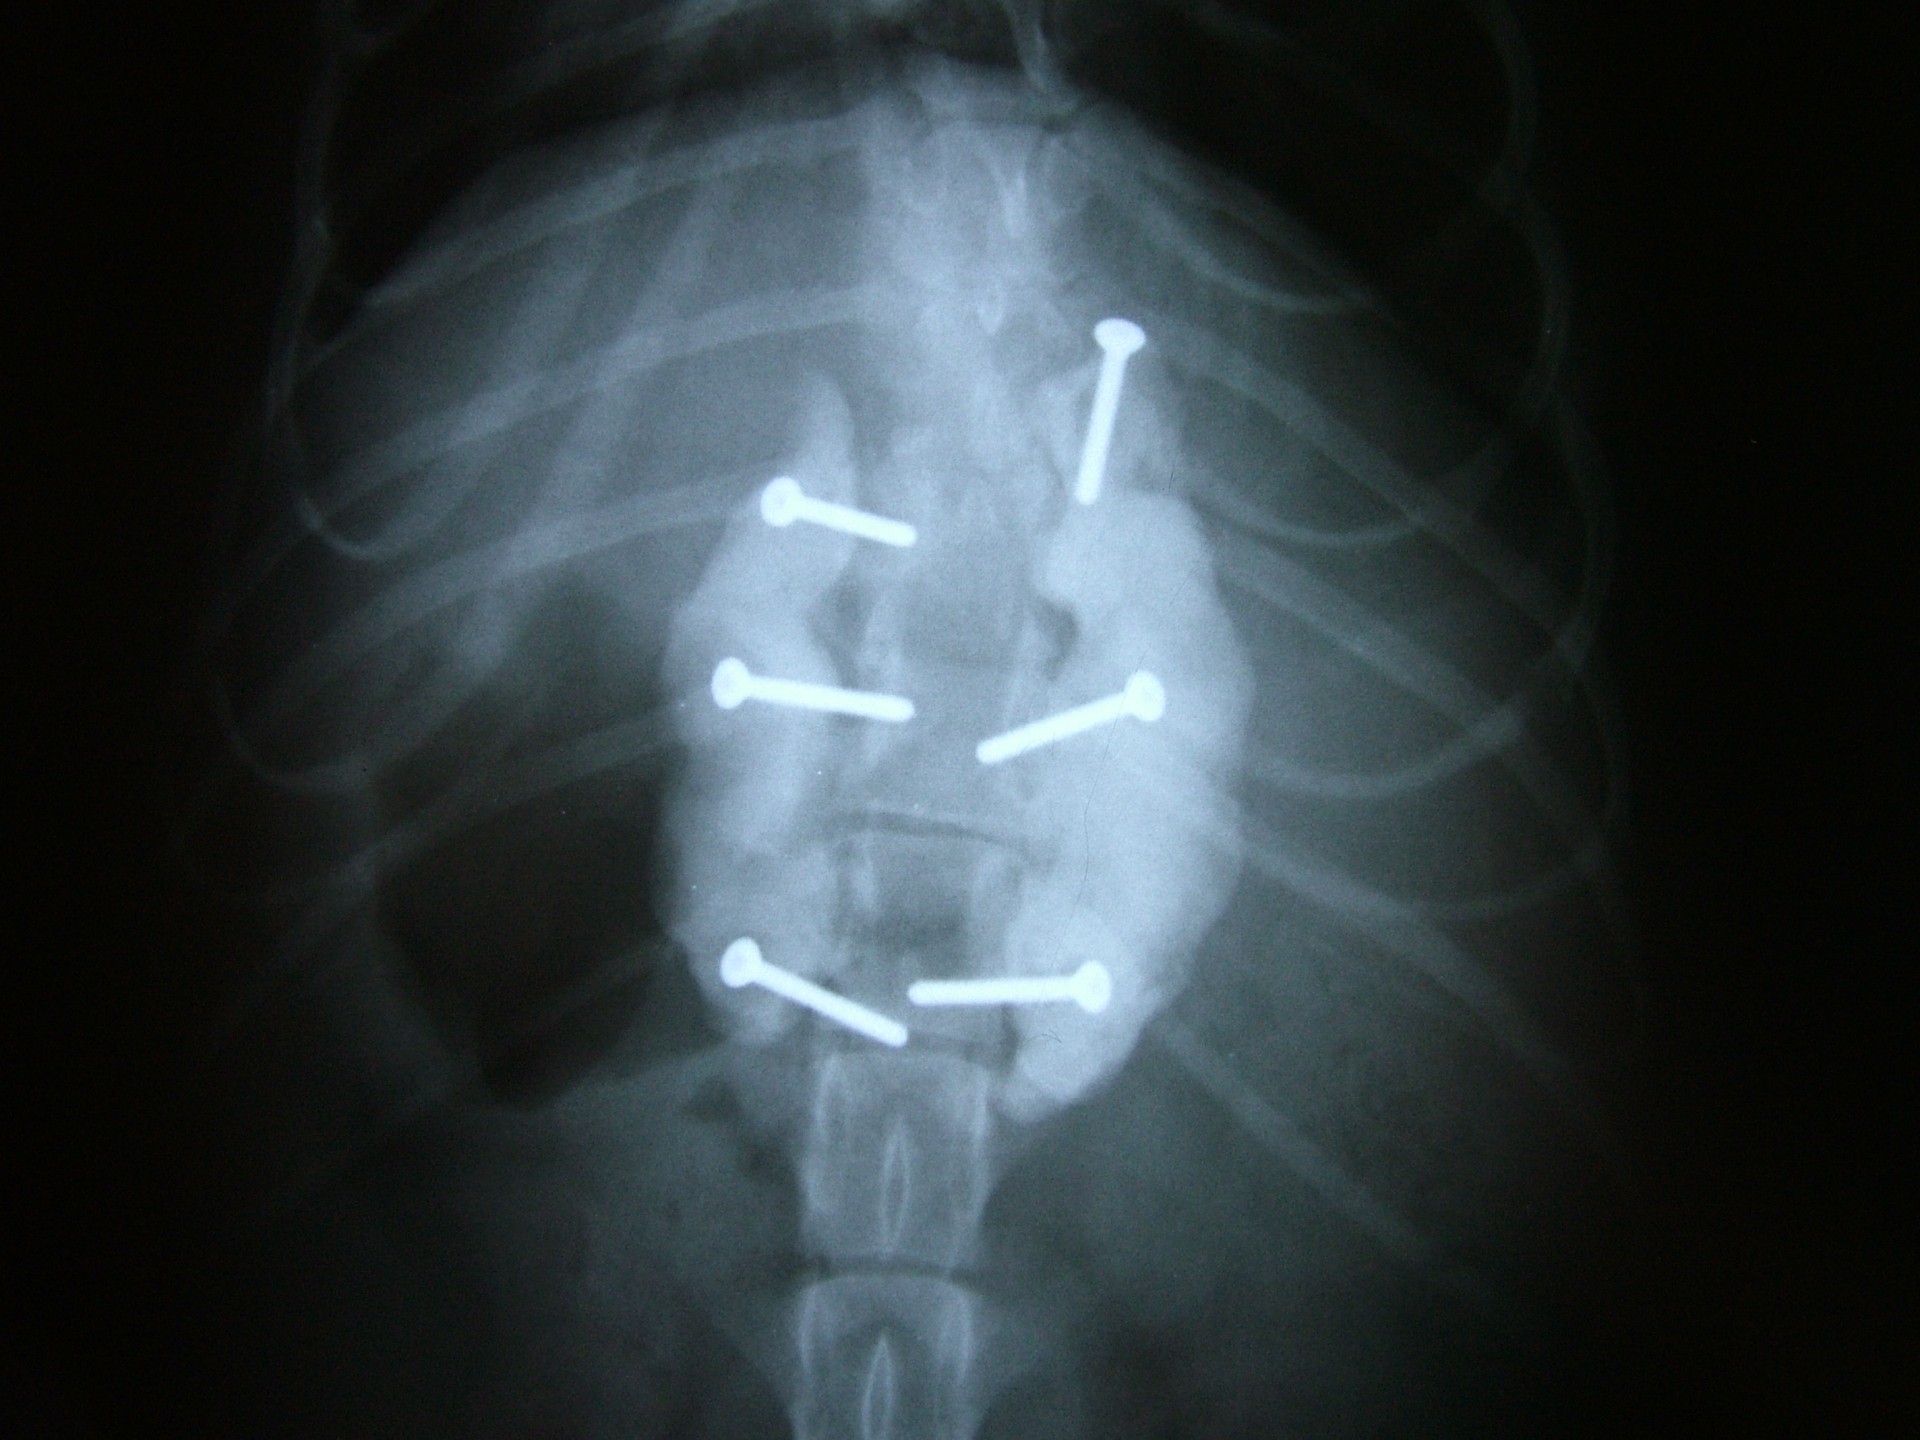

A törött csigolyatestek adaptációja és rögzítése a nyitott gerinccsatorna mellett komoly kihívást jelent. A későbbi elmozdulás elkerülésére többféle műtéttechnika alkalmazható, melyek közül a csigolyatestek lemezes osteosynthesise ill a fixateur interna használata terjedt el leginkább. Első esetben a sérülés előtti és mögötti csigolyákat lemez és csavarok segítségével egymáshoz rögzítjük, míg az utóbbi esetben a törés előtti és mögötti egy vagy több csigolyatestet két oldalról behelyezett csavarok és egy steril kétkomponensű akrilát műgyanta segítségével rögzítjük.

Bármilyen műtét után kialakulhat olyan szövődmény, mely gennykeltő baktériumok műtéti sebben történő elszaporodásával jár (szeptikus szövődmény). Különösen igaz ez olyan beavatkozásokra, amikor valamilyen idegen anyag (implantatum) kerül a szervezetbe beültetésre. Ilyen idegen anyag a gerinctörés műtéteknél használatos fixateur interna rögzítőanyaga (akrilát műgyanta) is. Abban az esetben, amikor a szeptikus szövődmény antibiotikumok célzott adásával nem gyógyítható, a test számára idegen anyagot el kell távolítanunk. A gerinctörés műtéténél ez a nyitott gerinccsatorna miatt fokozott kockázatot jelent. Az implantatum eltávolítását követően azonban a szeptikus folyamat gyógyul és a helyén kialakuló kötőszövet a fixateur externának megfelelően rögzíti a gyógyulófélben lévő csigolyát is.